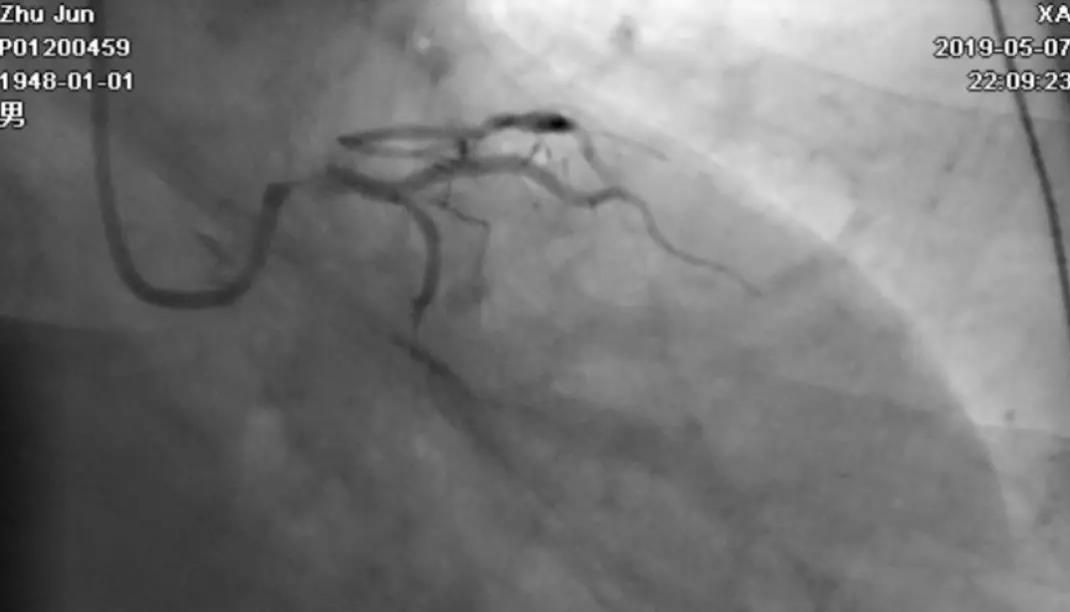

轻轻冒烟,证实指引导管到位

轻轻冒烟,大致了解前降支的情况

这一步相当重要。否则,无论是导管嵌顿,还是导管深插,稍不留意患者都有可能一招致命。